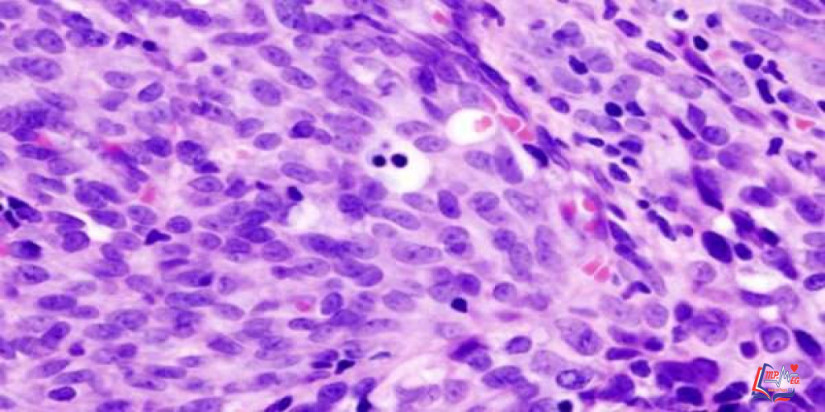

الساركوما الوعائية هي نوع نادر من السرطان يُصيب بطانة الأوعية الدموية و الليمفاوية، وتمثل الأوعية الليمفاوية جزء من الجهاز المناعي، يجمع البكتيريا والفيروسات والمواد الضارة، ثم تقوم بإخراجها من الجسم.

ليس من الواضح أسباب حدوث الساركوما الوعائية، ولكن تعَرف الأطباء على بعض عوامل الخطورة التي تُزيد نسبة حدوث المرض. ويعلم الأطباء أن شيئاً ما يحدث للخلايا التي تبطن الأوعية الدموية والليمفاوية، مما يؤدي إلى حدوث خلل في الكود الجيني. وهذا الخلل يأمر الخلية بالنمو بسرعة، مما يؤدي إلى زيادة عدد إنتاج الخلايا الغير طبيعية. وتلك الخلايا الغير طبيعية تستمر في البقاء عندما تموت بقية الخلايا.

والنتيجة هي تراكم الخلايا الغير طبيعية التي تنمو في الوعاء الدموي أو الليمفاوي المصاب، ومع الوقت، يمكن أن تنفصل تلك الخلايا وتهاجر إلى مناطق اخرى من الجسم.